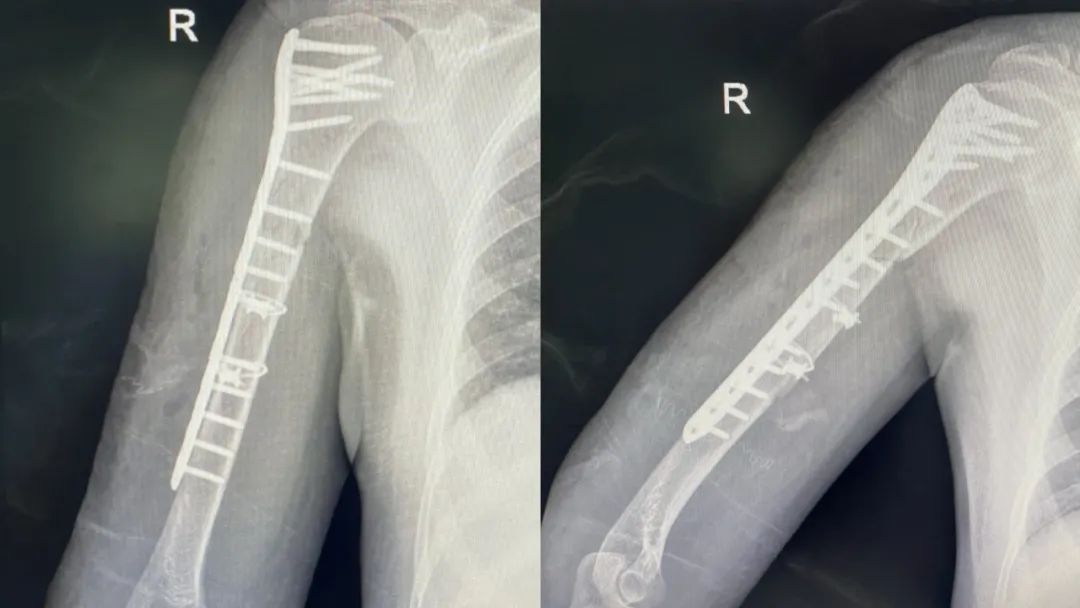

*患者术后X片

术后,吕豪副主任医师及医疗团队术后查看患者,患者一开始因恐惧而不敢锻炼,吕主任对患者进行耐心详细的解释,并指导患者进行患肢功能锻炼。术后第三天的时候,患者从骨折的痛苦中出走出来,患者可以进行耸肩、肩外展、曲肘等动作,患者及家属对于手术疗效非常满意,向吕主任医疗团队表达了由衷的感谢。